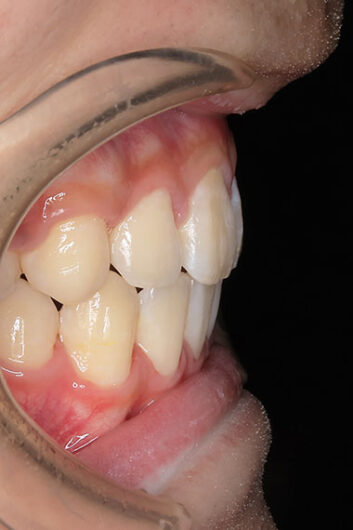

歯が重なっている、出っ歯を治したい 以前に治療した方からの紹介で来院した患者さんです。 上下顎前歯部の叢生(がたつき)、上下顎前歯の前方傾斜、 骨格的上顎前突傾向でした。 小児矯正で叢生の緩和を行い、 本格矯正で前方傾斜した前歯の改善を行いました。 マルチブラケット 動的治療期間 3年3か月 調整回数25回

平均来院間隔1.5か月に1度の来院でした。 治療後は後戻りの軽減するために、親知らず(第三大臼歯)の抜歯をお勧めしています。